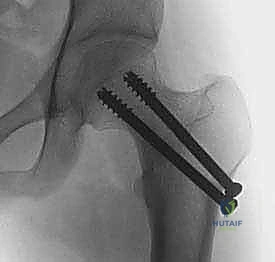

3. التثبيت الداخلي (Internal Fixation)

تُستخدم أدوات تثبيت خاصة بالأطفال. في الأطفال الأكبر سناً، تُستخدم مسامير مجوفة (Cannulated Screws) يتم إدخالها بدقة فائقة. يحرص الدكتور هطيف بصرامة على عدم اختراق صفائح النمو بالمسامير إلا إذا كانت الضرورة القصوى تقتضي ذلك (وفي هذه الحالة تُستخدم مسامير ملساء لتجنب إعاقة النمو).

قبل دخول غرفة العمليات، يقوم الدكتور هطيف بدراسة صور الأشعة وتحديد نوع وحجم المسامير أو الشرائح المناسبة لعمر الطفل وحجم عظامه، مع مراعاة مواقع صفائح النمو.

2. الرد المغلق أو المفتوح (Reduction)

- الرد المغلق: تحت التخدير العام، وبمساعدة جهاز الأشعة المرئية (C-arm)، يقوم الدكتور هطيف بتحريك الساق بلطف وبطريقة هندسية دقيقة لإعادة العظام المكسورة إلى مكانها دون فتح جراحي كبير. يتم تفريغ التجمع الدموي داخل المفصل (Capsulotomy) لتخفيف الضغط عن الأوعية الدموية.

- الرد المفتوح: إذا لم تنجح الطريقة المغلقة، أو إذا كان الكسر معقداً، يتم إجراء شق جراحي صغير ودقيق للوصول للكسر ورؤيته بالعين المجردة لضمان تطابق العظام بنسبة 100%.